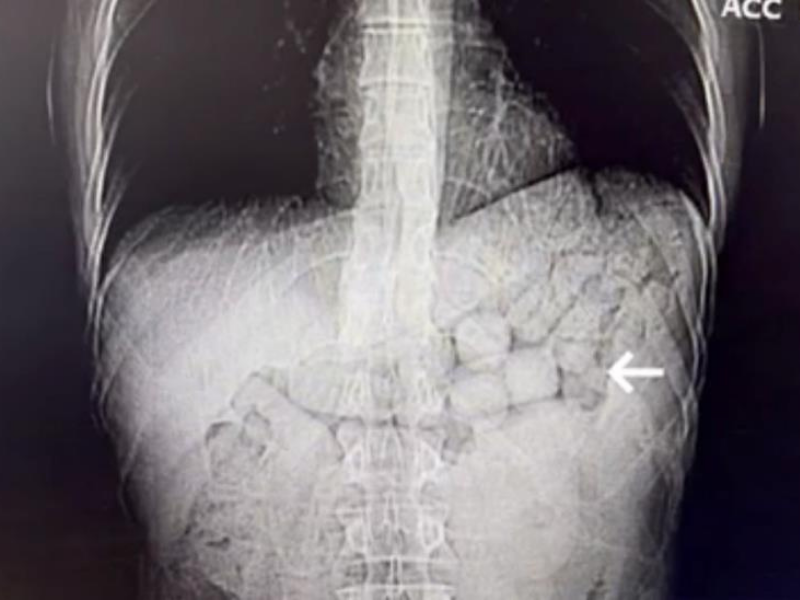

Şüphelilerin “yutma” yöntemiyle uyuşturucu taşıyor olabileceği değerlendirilerek sağlık kontrolleri için hastaneye sevk edildiği öğrenildi. Çekilen tomografi görüntülerinde mide ve bağırsak bölgelerinde yabancı cisimlere rastlandı.

91 KAPSÜL METAMFETAMİN ELE GEÇİRİLDİ

Yaklaşık 3 gün süren tıbbi takip sonucunda şüphelilerin vücudundan 91 kapsül halinde toplam 807,15 gram metamfetamin maddesi çıkarıldı. Ele geçirilen uyuşturucuya el konulurken, şüpheliler gözaltına alındı.